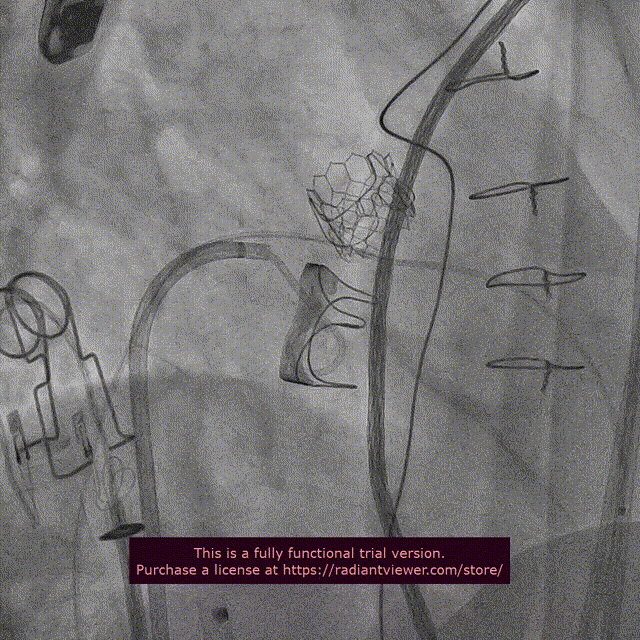

10. 双瓣植入后左室造影与主动脉根部造影

二尖瓣位SAPIEN 3植入后左室造影

双瓣SAPIEN 3瓣膜植入后主动脉根部造影

二尖瓣位和主动脉瓣位SAPIEN 3瓣膜功能良好

二尖瓣位SAPIEN 3瓣膜不影响左室流出道

无心包积液